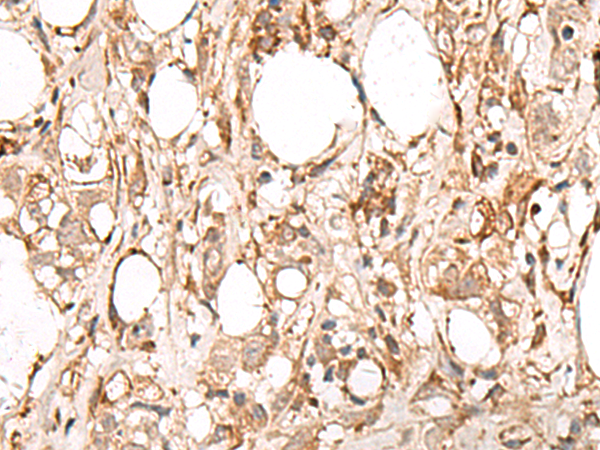

IHC (Immunohiostchemistry)

(The image is immunohistochemistry of paraffin-embedded Human breast cancer tissue using (FBXW8 Antibody) at dilution 1/65.)